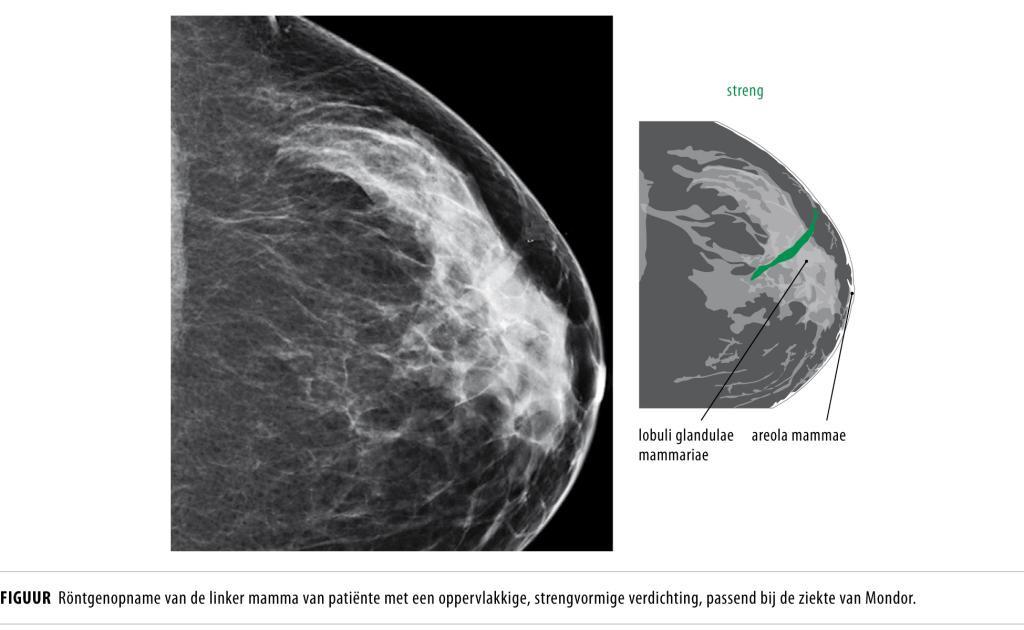

Een 36-jarige vrouw werd verwezen naar de polikliniek Heelkunde wegens een palpabele afwijking in de linker mamma. Bij lichamelijk onderzoek palpeerden wij een gevoelige streng lateraal van de tepelhof. Röntgenologisch en echografisch onderzoek van de linker borst toonden een oppervlakkige, strengvormige verdichting (figuur). Op basis van het klinisch beeld en het beeldvormend onderzoek stelden wij de ziekte van Mondor vast. Deze aandoening berust op ontsteking en trombosering van een oppervlakkige vene. Vaak betreft het venen in het subcutane vet van de mamma, maar ook aders van buik, romp of penis kunnen zijn aangedaan. Deze zeldzame vorm van tromboflebitis werd in 1939 voor het eerst beschreven door de Franse chirurg Henri. Meestal ontstaat spontaan een subcutaan gelegen, palpabele streng die aanvankelijk rood en bij aanraking gevoelig is, maar al snel wordt deze hard en verdwijnt de pijn. Eventuele retractie van de huid rond de borst moet niet in verband worden gebracht met een mammacarcinoom. De pathogenese is slechts ten dele bekend. De ziekte kan ontstaan na minimaal trauma, bijvoorbeeld een ongelukkige tilbeweging, of na mammachirurgie. Andere risicofactoren zijn extreme fysieke activiteit en infectie. De aandoening is zelflimiterend na 6-8 weken; onze patiënte was na 2 maanden klachtenvrij.

Figuur 1

Diagnose

Ziekte van Mondor.